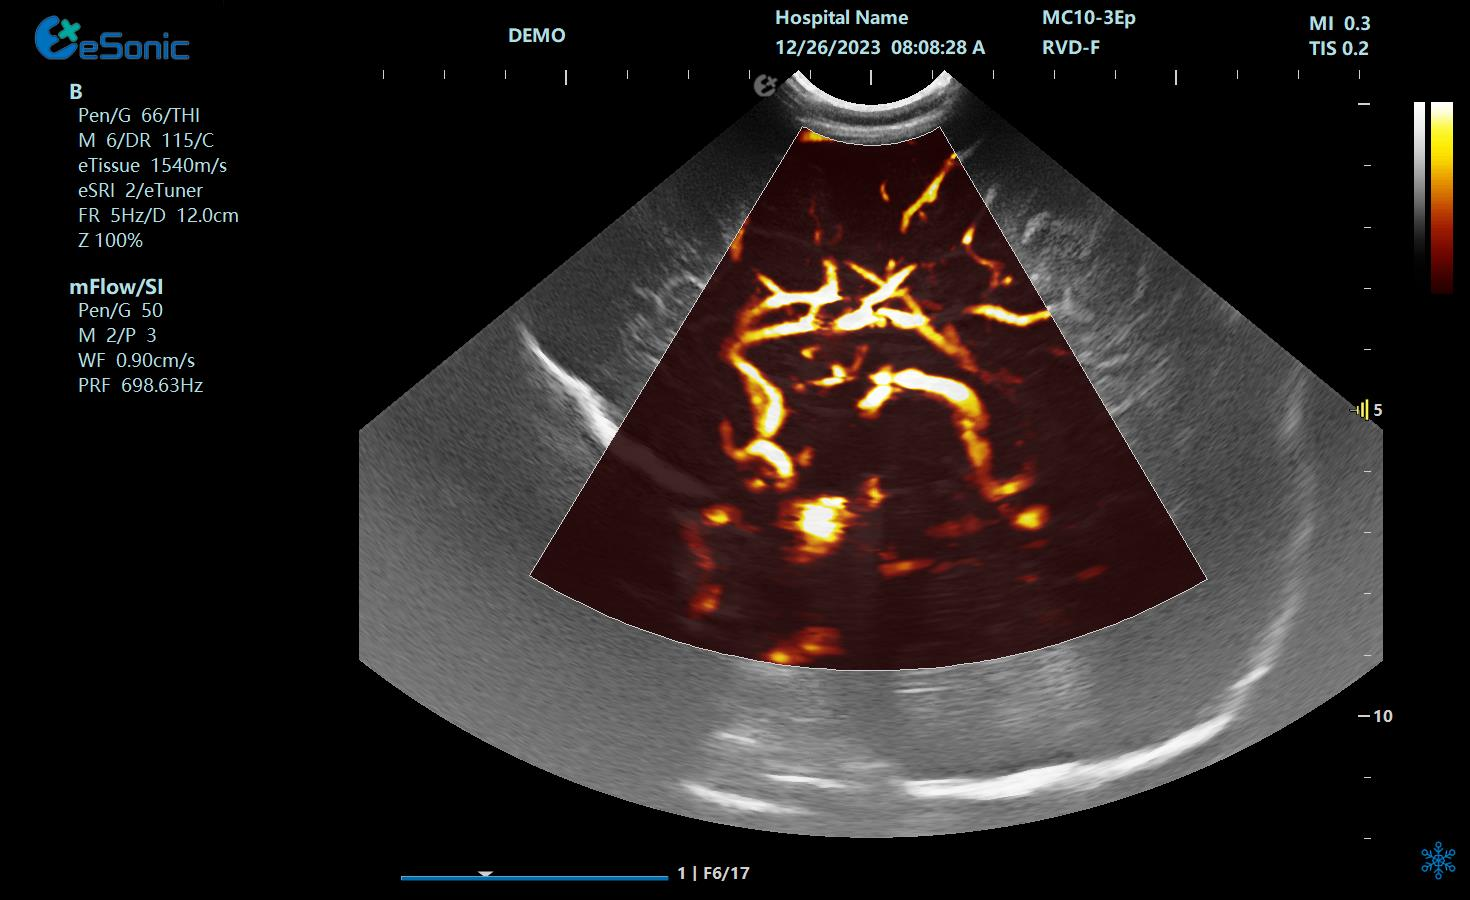

mFlow微血流显像技术,细节分辨率达100μm,支持频谱多普勒及VI血管指数定量。

mFlow新生儿颅脑